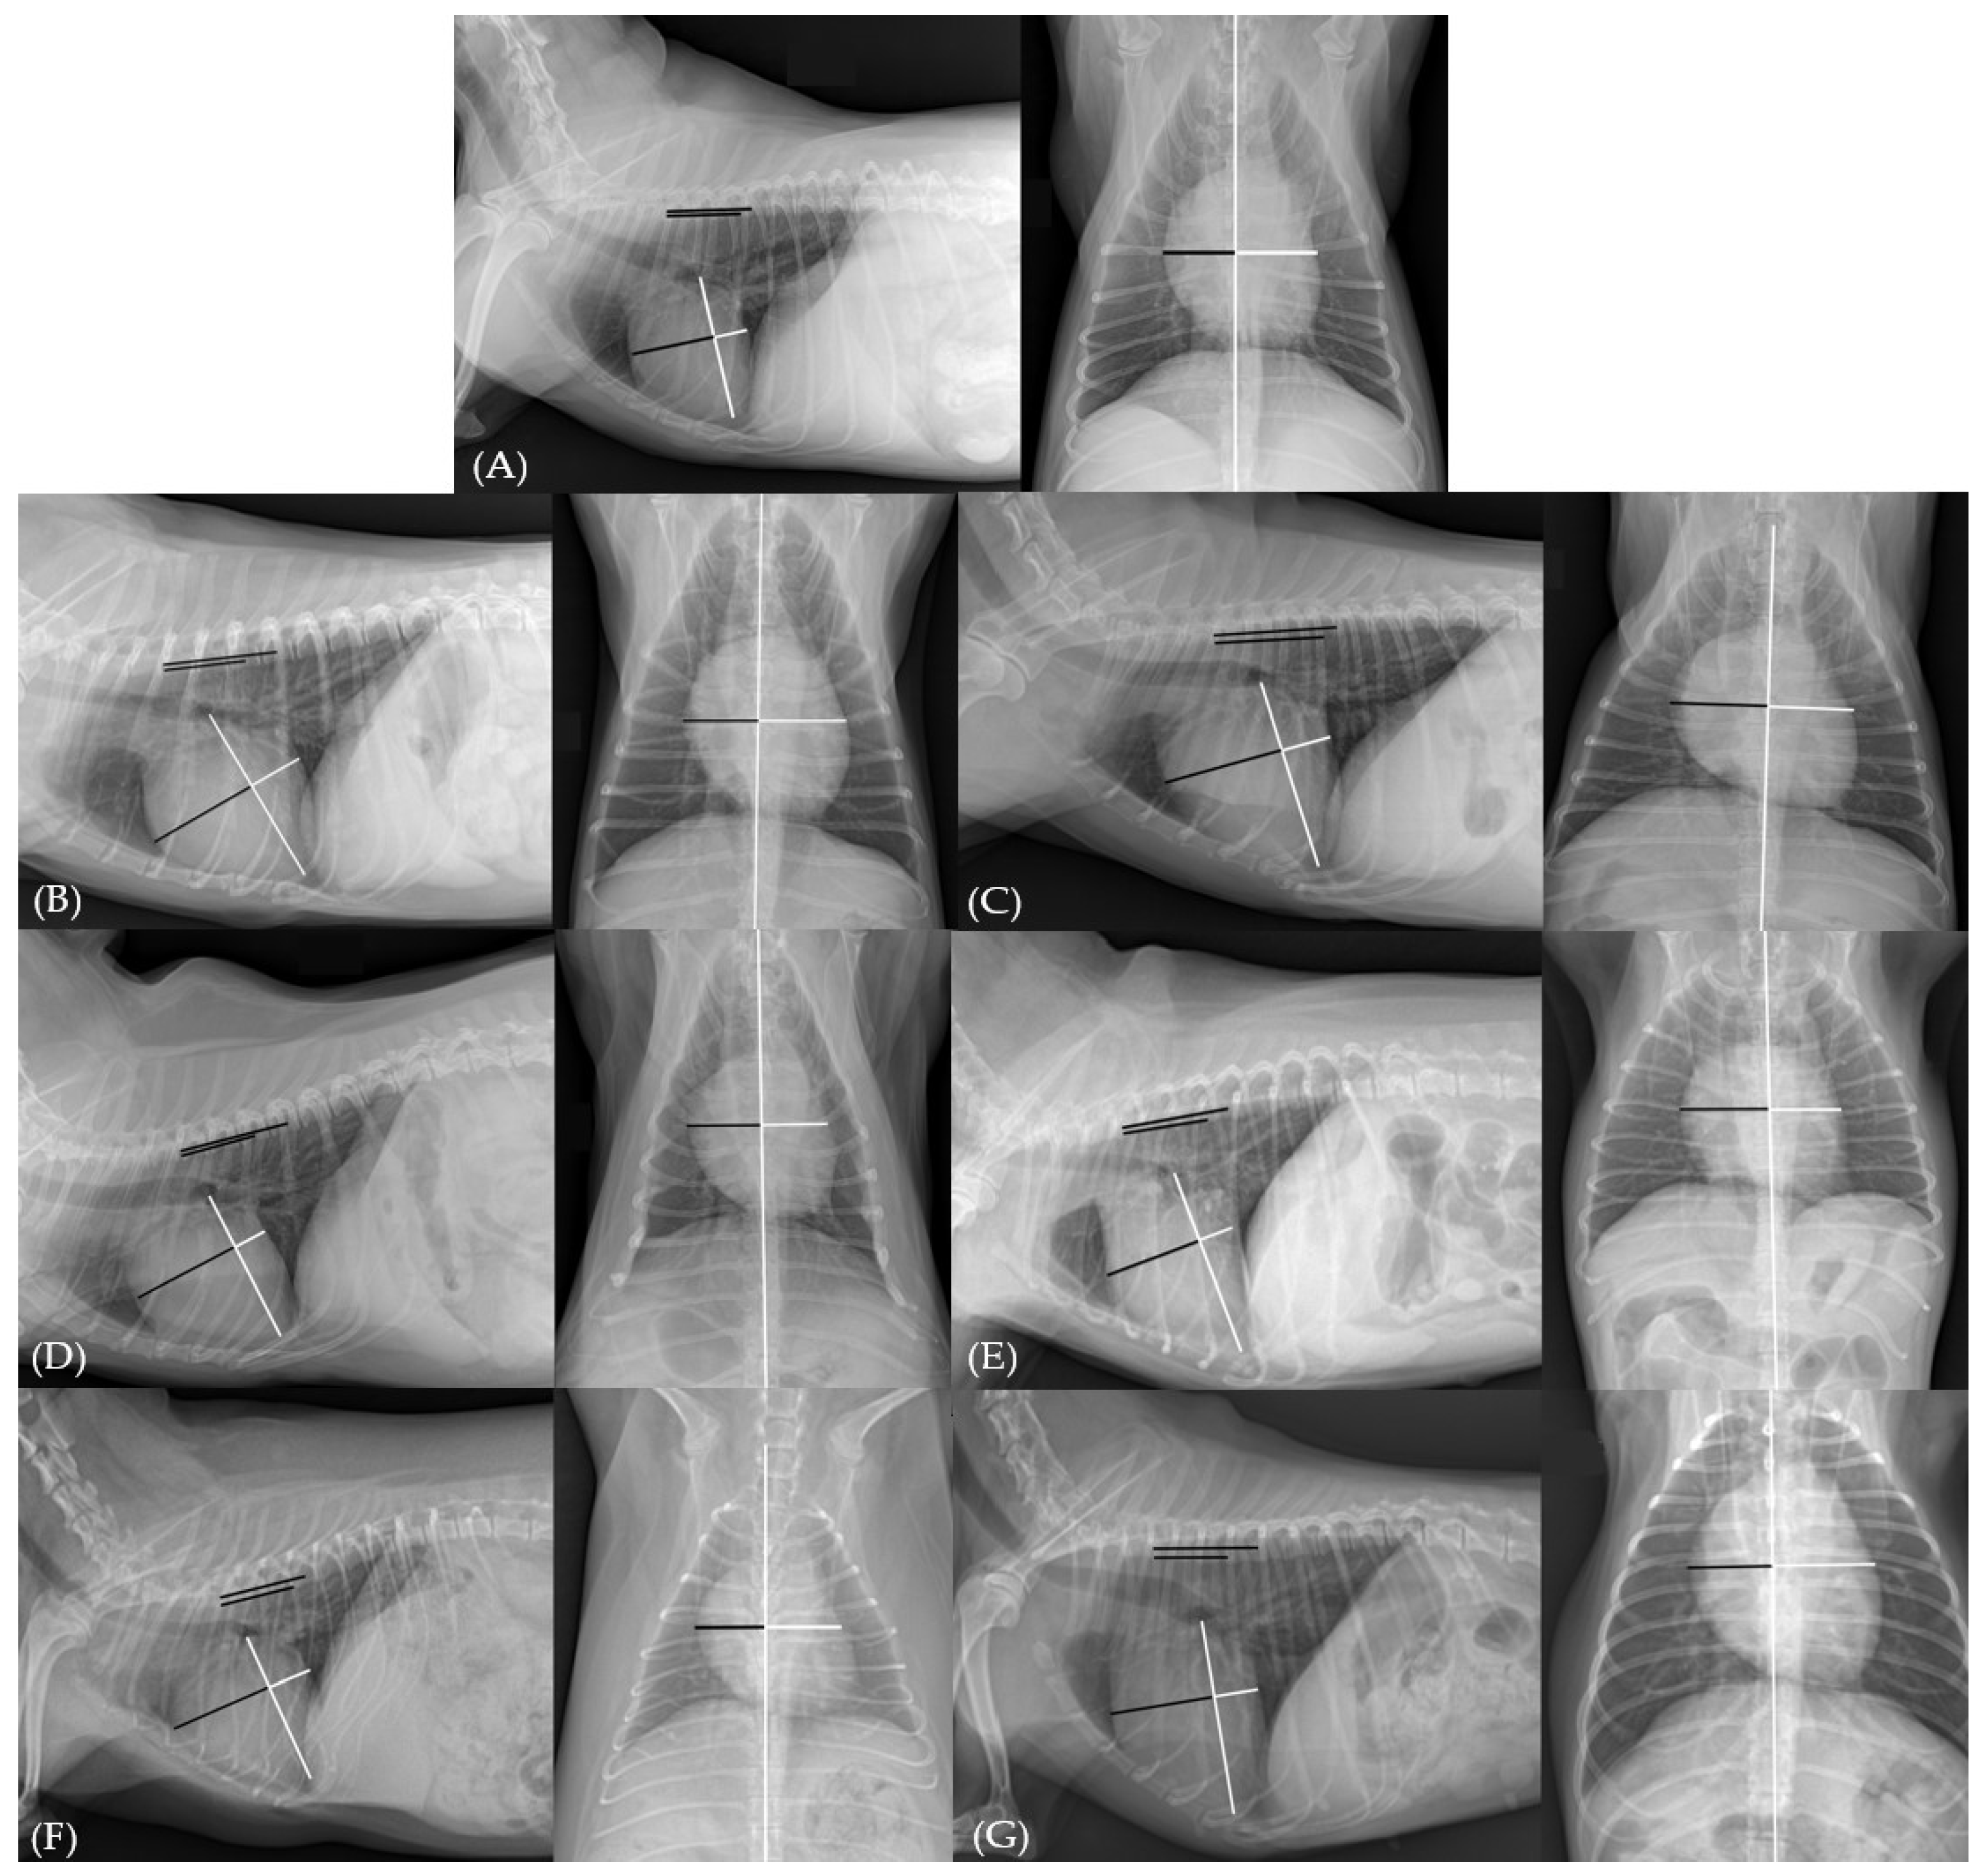

2.2. Data Collection and Thoracic Radiography Evaluation

3.2. Imaging and Statistical Analysis